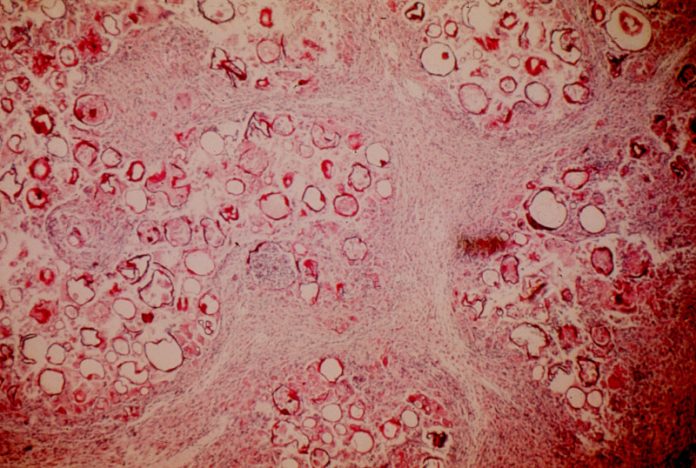

▲紅點為腫瘤細胞部位,比起其他正常細胞,腫瘤細胞電位差較低。(Photo Credit: Brook Chernet; Tufts University School of Arts and Sciences)